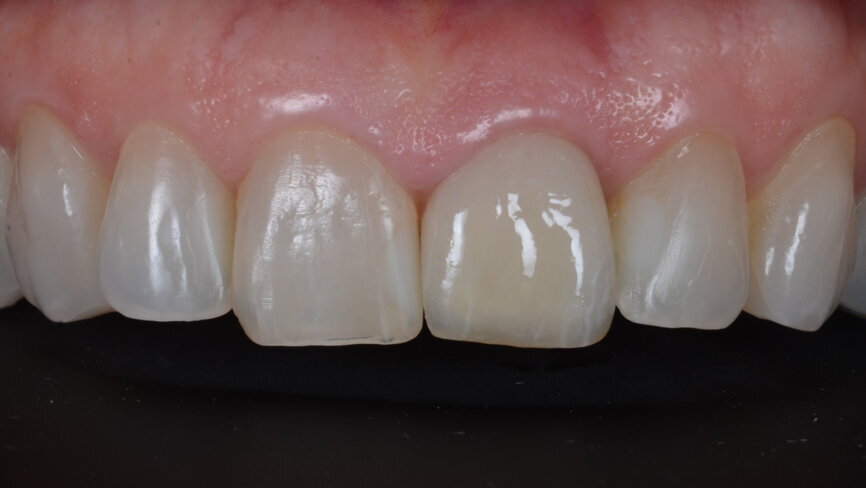

A 53-year-old female patient presented to the office with a fractured left central incisor which had been repeatedly bonded to a ceramic crown (Figs. 1 & 2). Anamneses and examination established good systemic and oral health, a well-balanced occlusion and no smoking habits. Cone beam computed tomography (CBCT) and a periapical radiograph showed external root resorption with very limited insertion into the alveolar bone, insufficient for adequate conventional intra-radicular post placement (Figs. 3 & 4). Considering that the fractured tooth was in the aesthetic zone, the patient requested restoration in the safest and fastest way possible.

Fig. 1: Initial situation, extra-oral view.

Fig. 2: Initial situation, intra-oral view.